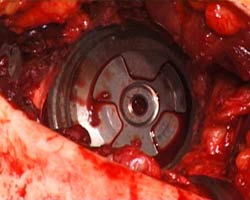

Abb. 6

Situation nach Einbringen des Polyäthylen-Keramikinlays

in die Titanpfanne (weiß: Polyäthylen, gelblich:

Keramik) |